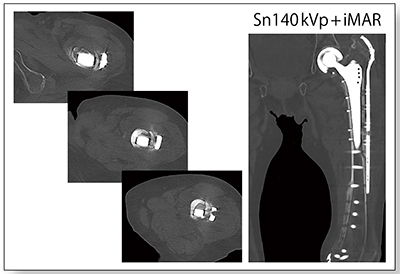

●金属アーチファクト低減

SOMATOM Driveでは“iMAR”(金属アーチファクト低減ソフトウェア)を使用できることに加え,Tin filterやDECTと組み合わせることで,金属アーチファクトをより低減することができる。iMARでは,ターゲットとするデバイス(コイルやインプラントなど)を選択して適用することで,最適なアーチファクト低減効果を得ることができる。

症例5は左人工骨頭ステム周囲骨折術後で,仮骨の状況などを詳細に観察するためCTを撮影した。iMARによりアーチファクトが抑制され,非常にクリアで評価しやすい画像を得ることができた(図5)。

図5 症例5:左人工骨頭ステム周囲骨折術後(77歳,女性)